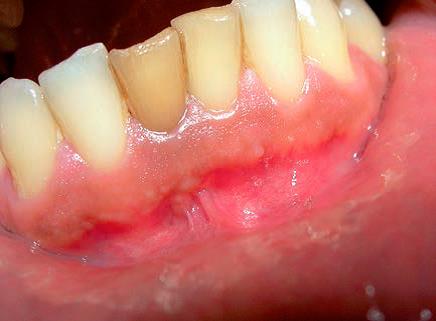

Ryc. 11. Zastosowano antyseptyczne leczenie kanałowe zęba 31. Po tygodniu przetoka uległa wygojeniu.

Źródło: Olczak K, Pawlicka H. Zastosowanie rentgenodiagnostyki w endodoncji. Mag Stomatol. 2019; 9: 30.

Jeszcze w stosunkowo niedalekiej przeszłości pokutowało wśród pacjentów (i niestety również wśród niektórych lekarzy dentystów) przekonanie, że zęby będące przyczyną stanów ropnych należy usunąć. Tymczasem można te zmiany skutecznie leczyć, a aktywny wysięk opanować czasami zaledwie w trakcie kilku dni (ryc. 9‑11). Dopiero w przypadku niepowodzenia terapii zachowawczej należy rozpatrzyć zastosowanie zabiegu endodontyczno‑chirurgicznego lub w skrajnych przypadkach usunięcie zęba. W wielu przypadkach można też przeprowadzić leczenie jednowizytowe, nawet jeśli występują przewlekłe zmiany zapalne w tkankach okołowierzchołkowych (20‑23). Gdy leczenie na jednej wizycie jest niemożliwe, najczęściej zaleca się stosowanie opatrunku na bazie wodorotlenku wapnia. Działanie lecznicze preparatów wodorotlenkowo‑wapniowych jest związane z ich wysokim pH oraz z uwalnianiem jonów wapniowych i hydroksylowych (21, 23). Jony hydroksylowe powodują obniżenie ciśnienia tlenu i wzrost pH w tkankach zmienionych zapalnie. Jony wapniowe stymulują fosfatazę zasadową do wytwarzania zębiny i naprawy kości oraz wpływają na miejscowe reakcje immunologiczne. Niskie ciśnienie i alkaliczne środowisko sprzyjają procesom mineralizacji naprawy. Bakteriobójcze działanie wodorotlenku wapnia polega na niszczeniu cytoplazmatycznej błony komórek bakteryjnych oraz destrukcji struktur białkowych i DNA (23).